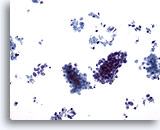

画像 4

肝FNA – 良性肝細胞

反応性変化を来した肝細胞。核は大小不同で、二核を有しています。

40倍

画像 4

肝FNA – 良性肝細胞

反応性変化を来した肝細胞。核は大小不同で、二核を有しています。

40倍